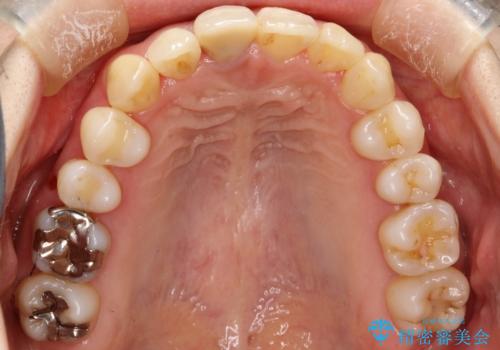

上下のガタガタのマウスピースによる非抜歯矯正

- 上下のがたつきを主訴に来院された患者様です。

上下の前歯と奥歯にがたつきがありました。

上下の奥歯を後方に移動させるのと、歯と歯の間をわずかに削ることでスペースを作り、歯を並べる計画としました。

比較的がたがたの度合いが大きかったですが、しっかりとマウスピースを使用していただけたので、順調に治療を終えることができました。